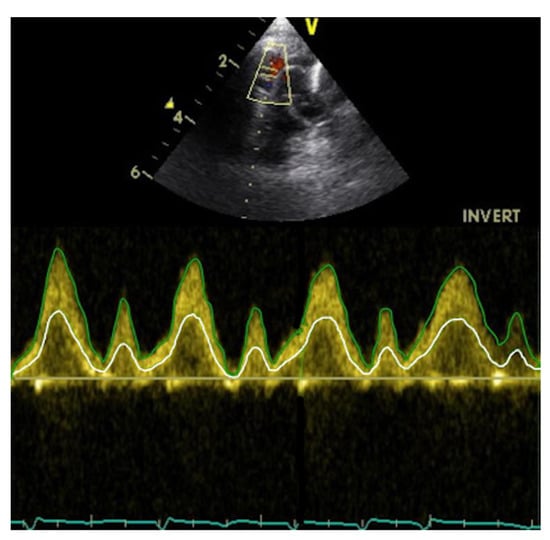

SVC flow velocity was assessed from a suprasternal view following the SVC from its origin at the innominate vein confluence to the right atrium. Angle correction of flow velocity was not used. The PWD gate was placed at the level of the RPA. VTI was calculated offline from SVC peak velocity (Figure 3).

SVC flow velocity was assessed from a suprasternal view as in Method 2, but in this case VTI was calculated from the instantaneous mean velocity rather than the instantaneous peak velocity. Measures were made off-line with Tomtec Arena, version TTA2 41.00, (Tomtec, Unterschleißheim, Germany) (Figure 3).

Figure 3. Spectral Doppler profile of blood flow velocity in the SVC, assessed from a suprasternal view. The green line represents the peak blood flow velocity, the white line the mean blood flow velocity.